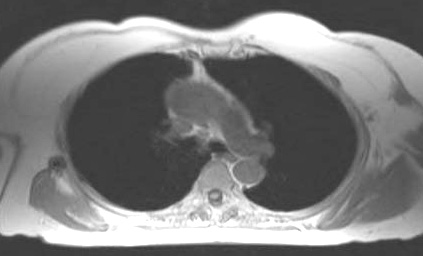

Imagerie par resonance magnetique IRM : Un coupe horizontal a travers D5 . Aort ascendent , descendent , veine cave superieure , trache et oesophage sont bien en voyaient .  Tronc medulaire et les muscle lateral , posterieure de la colonne vertebrale sont bien detecte ...